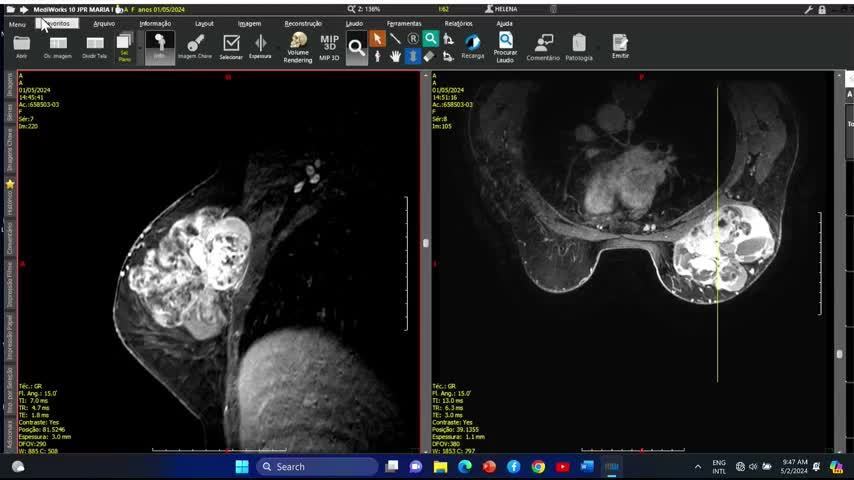

Interpretação e Pós-processamento das...

Interpretação e Pós-processamento das Imagens de RM na Workstation

Entendendo as Sequências do Exame de ...

Entendendo as Sequências do Exame de IRM das Mamas